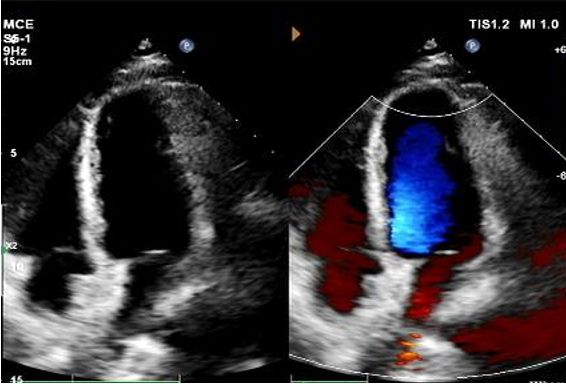

Today, we share a remarkable case highlighting 1-year post-op outcomes of MemoSorb in treating a complex long-tunnel PFO (12mm length, 1.4mm width), with a focus on serial echocardiographic evidence of device degradation and clinical symptom resolution.

Hari 1 sampai 9 bulan:

Tidak ada sisa shunt muncul.

Pengurangan bertahap pada kesopanan perangkat.